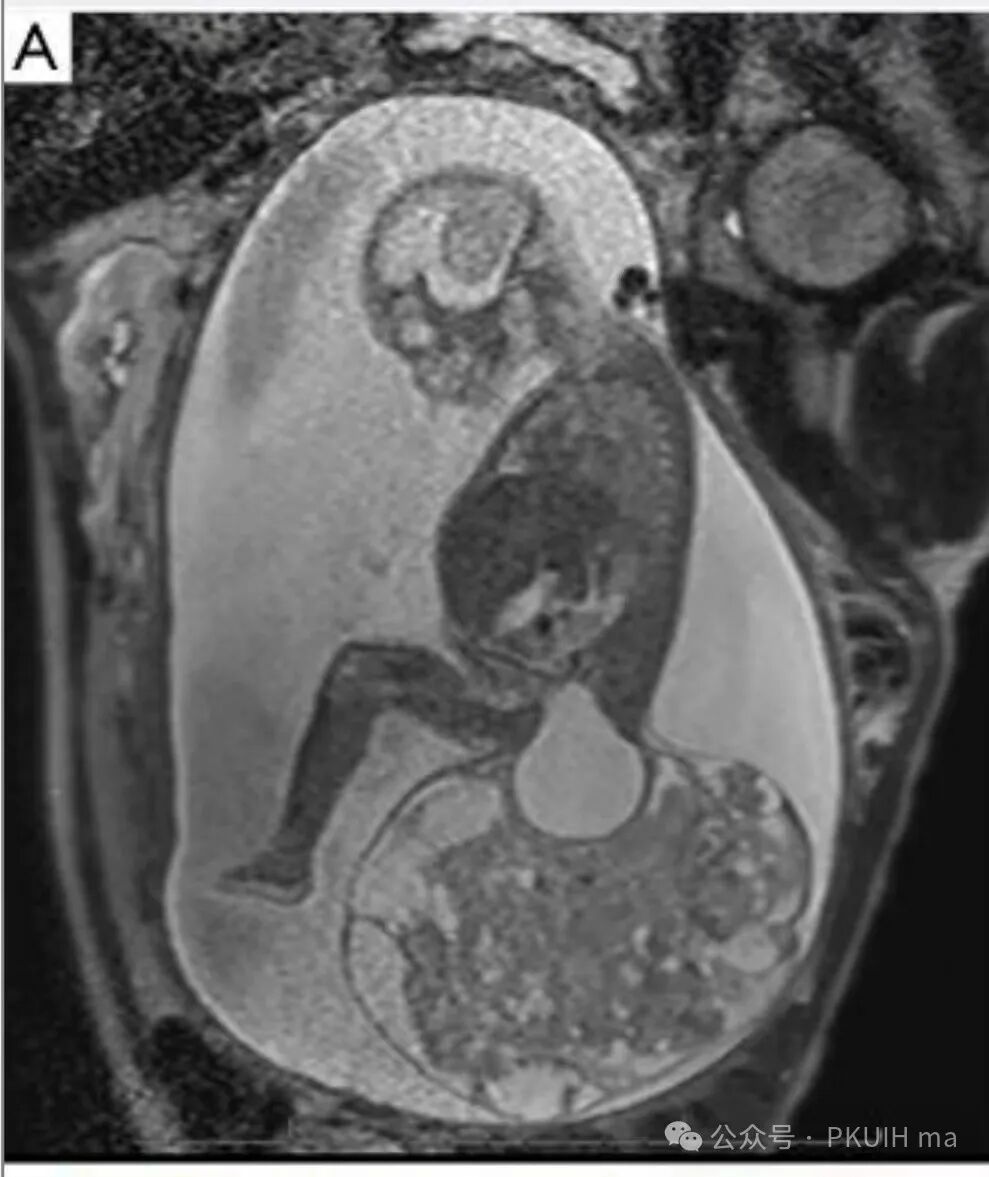

上图是25周胎儿骶尾部巨大畸胎瘤的核磁成像